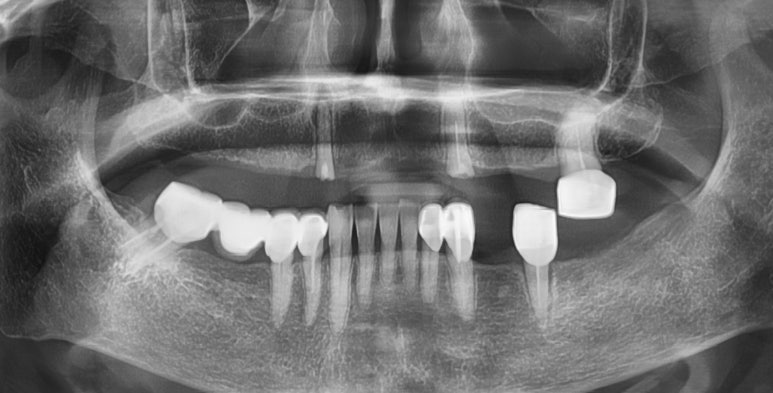

기존의 다른 치아와 다른 임플란트, 보철물과 조화를 이루는 앞니 임플란트

완성된 입안에서의 모습 사진입니다.

화살표 표시한 부분내의 치아가 이번에 진행한 임플란트입니다.